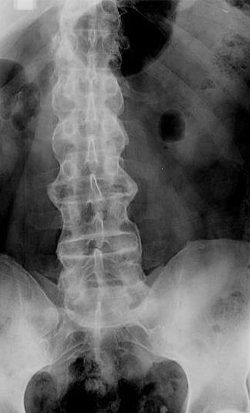

En la radiografía lumbar se observa lo siguiente:

La espondilitis anquilosante es una enfermedad inflamatoria crónica del raquis que afecta en todos los casos a las articulaciones sacroilíacas y, con menor frecuencia, a las articulaciones periféricas, además de que evoluciona con una acusada tendencia a la anquilosis. Es más frecuente en varones. Suele comenzar entre los 15 y 30 años. En más del 80% de los pacientes el inicio es insidioso. El dolor lumbar es el síntoma inicial, causando una sensación de rigidez en las nalgas y la cara posterior de los muslos, que corresponde a la inflamación de la región lumbar y de las articulaciones sacroilíacas. Es un dolor de carácter inflamatorio que empeora con el reposo. Los reactantes de fase aguda como la VSG y la PCR pueden estar elevados durante la enfermedad activa.1